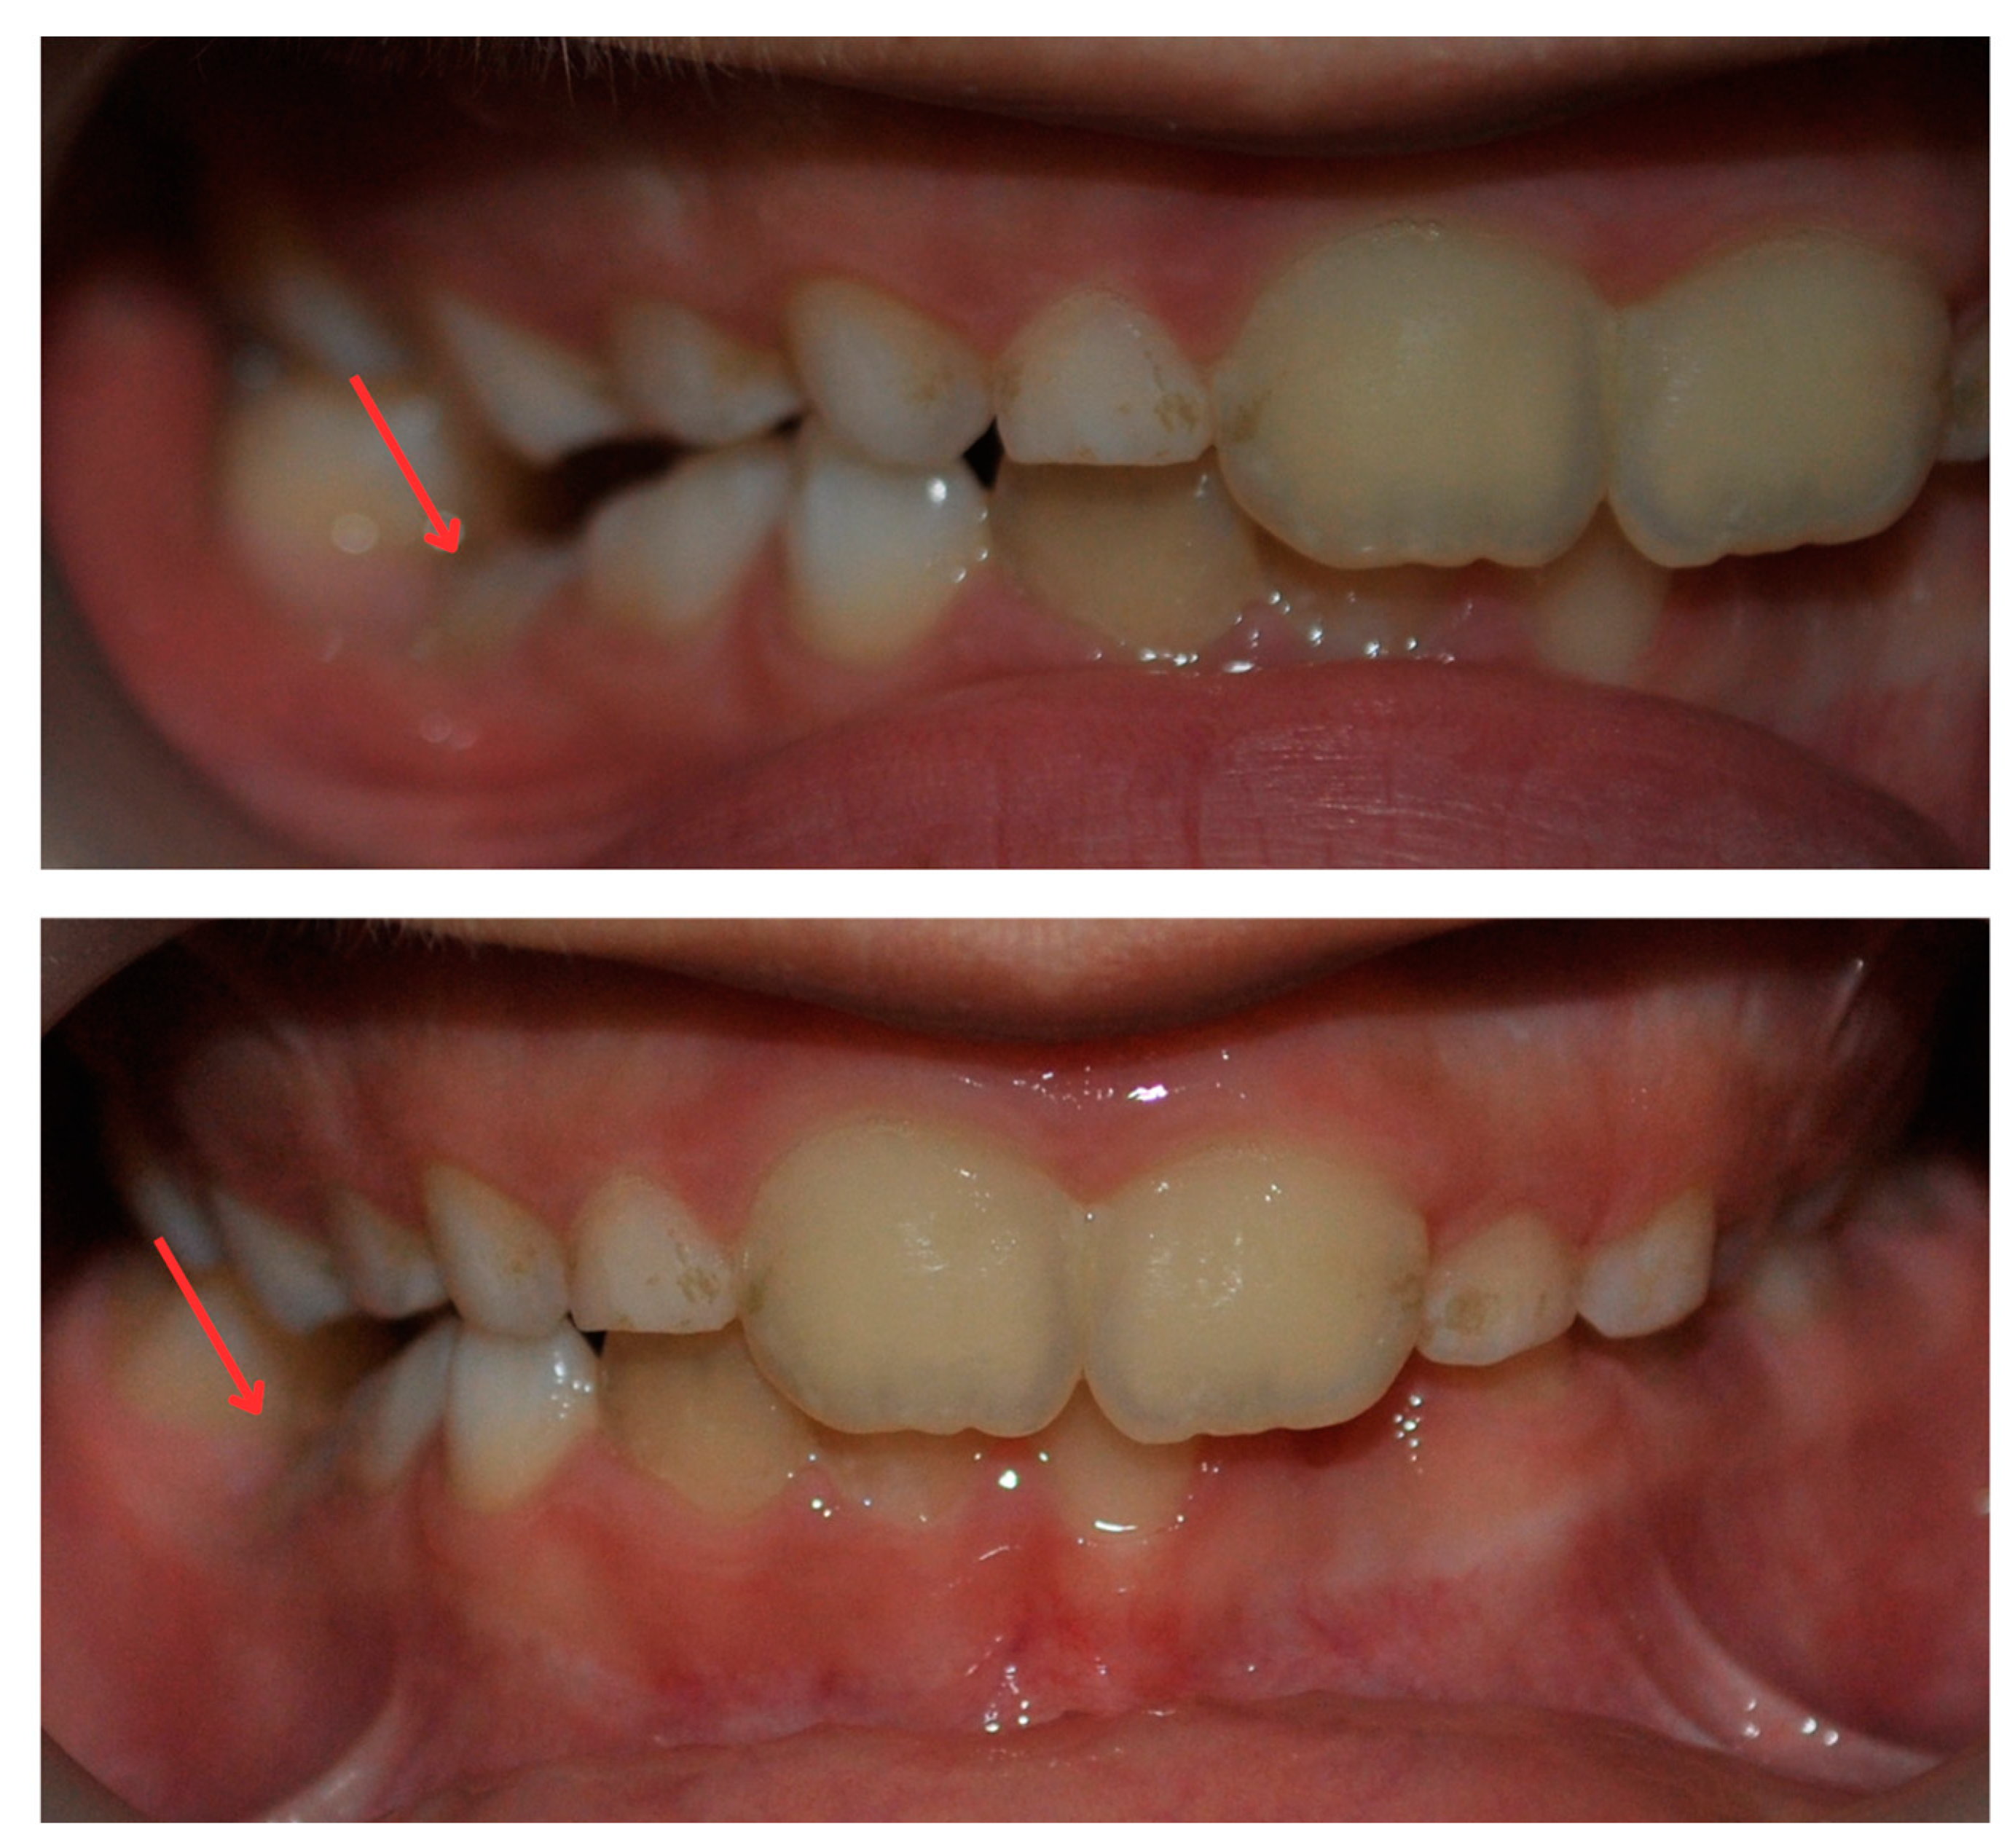

2. Case Report

2.3. Treatment Progress